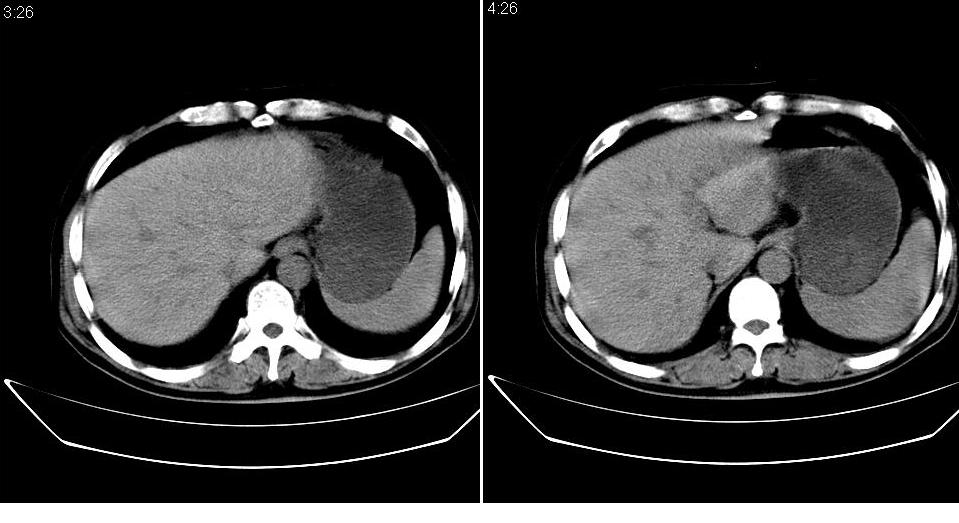

男 48岁,09年8月份在上级医院确诊胰头癌,准备在我院化疗。

胰头体积增大内见低密度影考虑为占位,肿瘤性病变可能性大。

胰头体积增大,外形不规则,密度欠均,支持胰头癌可能性大。